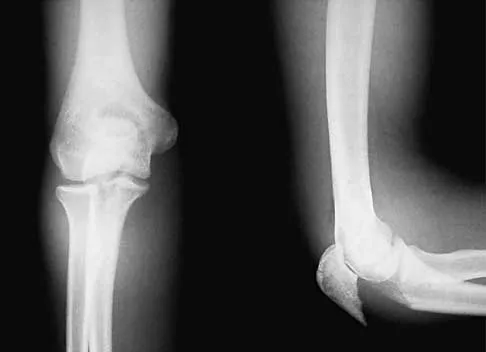

Master AAOS, ABOS, and OITE exams with Trauma Board Review MCQs (Set 4). Focus on high-yield questions for ti…

Master AAOS & ABOS boards with practice MCQs for Set 3, covering diagnosis & management of long bone fracture…

Master AAOS & ABOS boards with practice MCQs from Set 2, focusing on high-yield orthopedic trauma topics like…

Master AAOS, ABOS & OITE exams with Trauma 2000 MCQs (Set 1). Practice on femur, tibia fractures, open fractu…